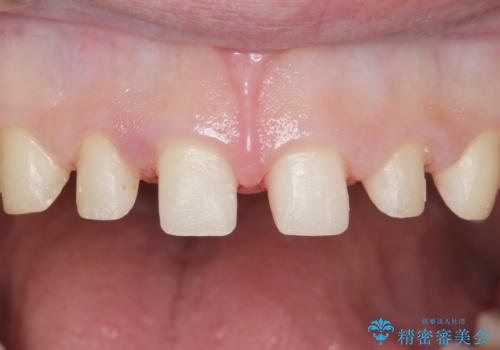

見た目と咬み合わせを改善するため、セラミッククラウンによる治療を行いました。

クラウンの種類:オールセラミッククラウン スタンダード